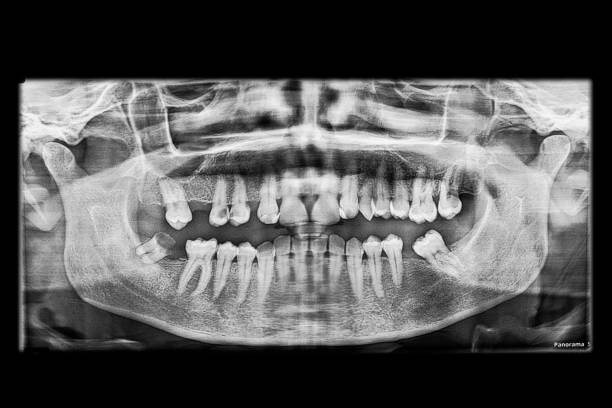

بسیاری از ما تجربه عصبکشی را داریم، یا حداقل کسی را میشناسیم که این درمان را انجام داده است. اما آیا میدانید پشت این واژه ساده، چقدر ظرافت و دقت نهفته است؟ درمان ریشه یا اندودانتیکس، فرآیندی پیچیده برای نجات دندانی است که مغز آن (پالپ) دچار عفونت یا التهاب برگشتناپذیر شده. هدف اصلی این درمان، پاکسازی کامل سیستم کانال ریشه از باکتریها و بافتهای عفونی، شکلدهی و سپس پر کردن آن با مواد زیستسازگار است تا از ورود مجدد باکتریها جلوگیری شود. ساده به نظر میرسد، نه؟ اما در واقعیت، کانالهای ریشه مثل هزارتویی هستند با انشعابات و زوایای پنهان که دسترسی به تمام آنها واقعاً یک چالش بزرگ است.

بزرگترین چالش در درمان ریشه، همین دسترسی و پاکسازی کامل است. دندانپزشک باید مطمئن شود که هیچ باکتری یا بافت عفونی کوچکی در هیچ گوشه و کناری باقی نمانده باشد. کوچکترین غفلت میتواند منجر به آبسه بعد عصب کشی شود. تصور کنید یک سیستم پیچیده را که باید بدون دید مستقیم و فقط با تکیه بر حس و ابزارهای بسیار ظریف، کاملاً تمیز کنید. اینجاست که اهمیت ابزارهای پیشرفته و دقیق به چشم میآید. کانالهای دندان ممکن است بسیار باریک، خمیده یا حتی در بعضی موارد، کلسیفیه (سختشده) باشند که این موضوع کار را برای ابزارهای سنتی بسیار دشوار میکند.

فناوریهای جدید در دندانپزشکی، مثل ظهور ابزارهای نیکل-تیتانیوم، موتورهای روتاری، و سیستمهای تصویربرداری پیشرفته، تا حد زیادی به رفع این چالشها کمک کردهاند. اما همیشه جایی برای بهتر شدن هست. مثلاً، کنترل دقیق عمق و جهت سوراخ کردن یا فرمدهی کانالها، هنوز هم به مهارت و ابزار بینهایت دقیق نیاز دارد. هدف، همواره به حداقل رساندن خطای انسانی و افزایش پیشبینیپذیری نتایج است. اینکه بتوانیم با اطمینان کامل بگوییم که کانالها کاملاً پاک و مهر و موم شدهاند، چیزی است که آرامش را هم برای دندانپزشک و هم برای بیمار به ارمغان میآورد. اینجا دقیقاً همان نقطهای است که ابزارهای جراحی مدرن، مانند کیت جراحی 3A، وارد صحنه میشوند تا این ظرافتها و چالشها را به بهترین شکل ممکن مدیریت کنند.